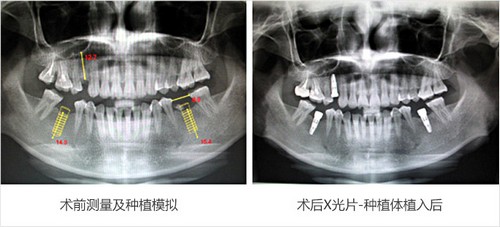

所以,缺牙较 好在三个月内种上,此时牙槽骨条件较好,进行种植修复有利于骨结合。而较 佳的时期,是即拔、即种,此时口腔内所有数值是较 佳的,这个时候种牙,省心、省时、省钱。

为全面保障手术质量,我院也不断引进新的医疗设备,除了斥资引进进口CT、种植机等设备,更是新添了“笑气镇痛系统”、“自体牙研磨骨粉”等设备,为不同需求的种植牙患者提供更加人性化的服务。